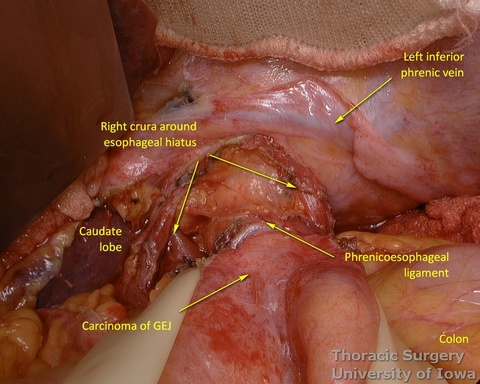

- Phrenoeosophagial ligament is formed by the transversalis fascia of abdomen and endothoracic fascia and is covered with the peritoneum. Thicker upper leaflet ascends obliquely and fuses with the adventitia of the esophagus above the diaphragm. The thinner lower leaflet runs caudally and attaches to the esophageal wall just cranial to the angle of His. The triangular space between the leaflets is filled with the perihiatal fat pad.

- The peritoneum is incised around the hiatus.

- The phrenoesophageal ligament is divided and the right crus dissected.

- Subhiatal fat ring is exposed after division of the lower leaflet of the phrenoesophageal ligament

- The abdominal esophagus, periesophageal fat, and nodes are dissected and encircled with a Penrose drain for retraction.